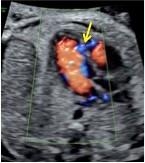

As part of your evaluation for CHD, we will complete a Level II ultrasound screening for other structural concerns your baby may have. In addition, our onsite Pediatric Echocardiography Lab enables your unborn child to benefit from the most advanced cardiac imaging technology currently available.

Our team offers a full range of options for evaluation of your baby including Level II fetal ultrasound, fetal echocardiography, and fetal MRI. UR Medicine also offers the only fetal MRI center in the Rochester metropolitan area and surrounding region to help evaluate many complex fetal conditions and placenta abnormalities.

UR Medicine’s ultrasound unit is certified by the American Institute of Ultrasound in Medicine to perform Level 2 ultrasounds, a more in-depth evaluation. Our experienced Registered Diagnostic Medical Sonographers and state-of-the-art equipment, including 3D/4D capabilities, help diagnose your developing baby with even more precision.